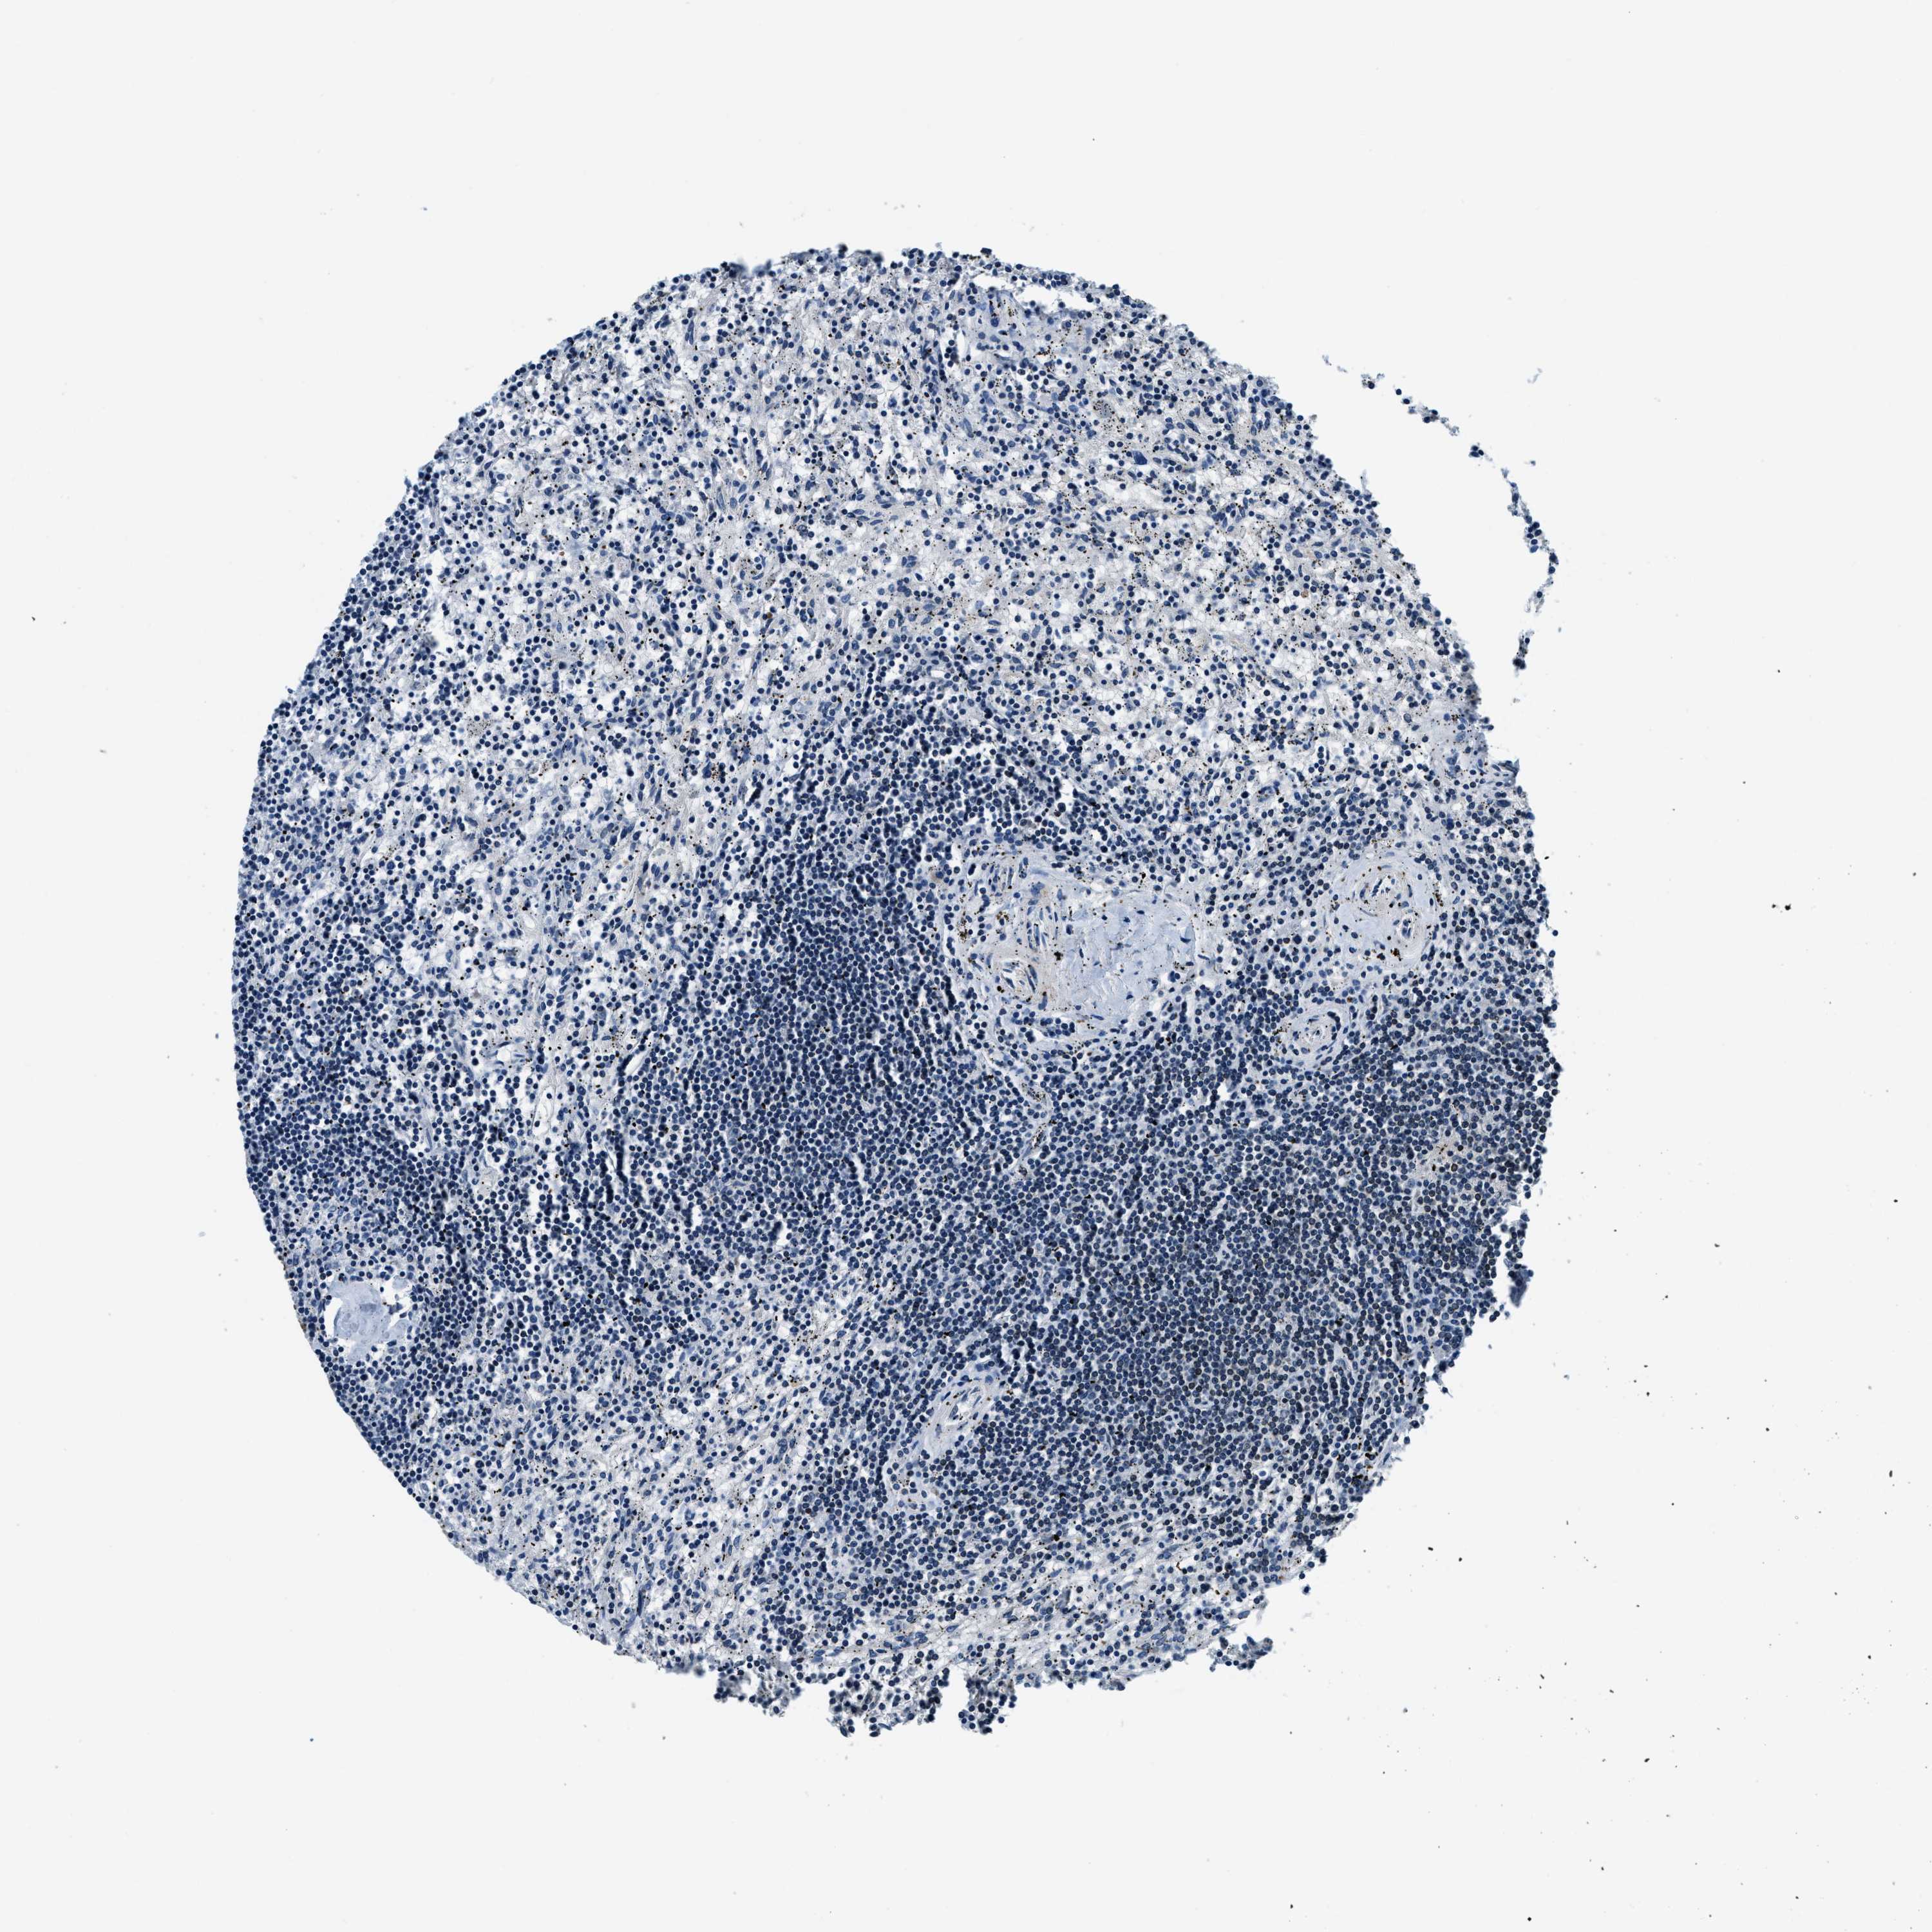

LYMPHOMA - Protein expressioni

A mouse-over function shows sample information and annotation data. Click on an image to view it in a full screen mode. Samples can be filtered based on level of antibody staining by selecting one or several of the following categories: high, medium, low and not detected. The assay and annotation is described here.

Each image is clickable and will lead to virtual microscopy that enables deeper exploration of all samples and also displays staining intensity scores, fraction scores and subcellular localization as well as patient and tissue information for each sample.

Antibody HPA019698

Staining

Medium

Intensity

Weak

Quantity

<25%

Location

None

Hodgkin's disease, NOS

Malignant lymphoma, non-Hodgkin's type, High grade

Malignant lymphoma, non-Hodgkin's type, Low grade